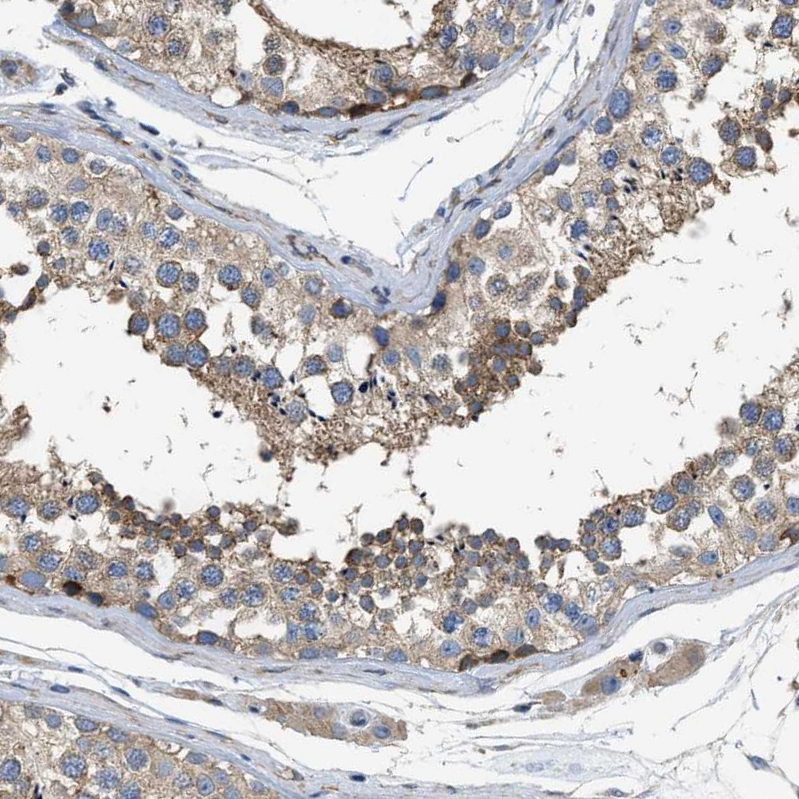

Immunohistochemical staining of human testis shows moderate cytoplasmic positivity in cells in seminiferous ducts.